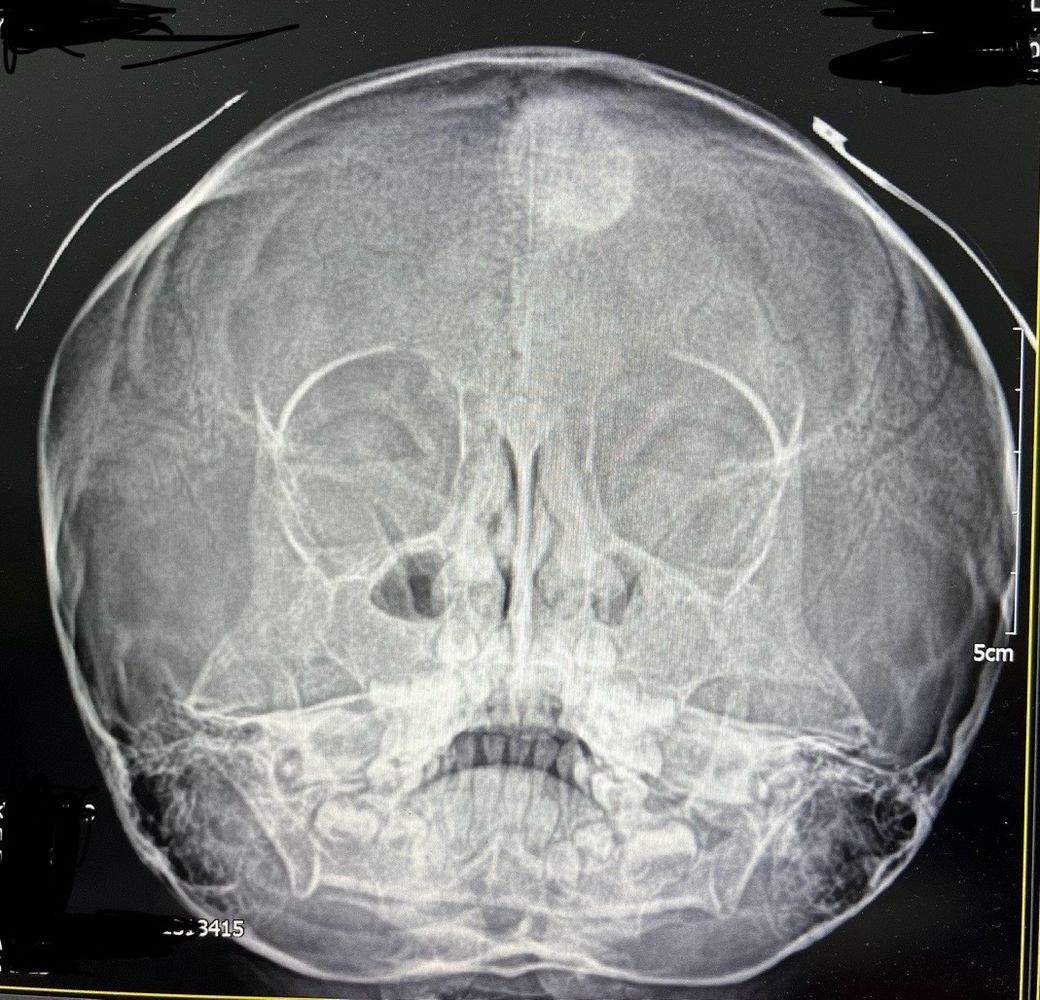

5세 여아입니다 얼마전 부비동 엑스레이사진 입니다

머리에 흰색 원이 보이는데요

소아과 원장님도 처음 보는거라시네요

무엇일까요?

진료 보려면 무슨과가 좋을까요?

• 1번 째 사진

아이의 X-ray 병변에 대해 걱정이신 듯합니다.

두개골 또는 뇌의 CT 검사가 필요할 것으로 생각됩니다.

CT 검사가 가능한 규모의 병원(종합병원 등)에 내원하셔서,

소아청소년과 또는 신경외과 의료진과 상의하시길 권장드립니다.

• 해당 소견과 관련하여서는 신경외과로 가셔서 보다 정밀한 검사를 받아보시는 것이 필요하겠습니다. 엑스레이 사진에서 분명 이상 소견이 있어 보이긴 하지만 해당 검사 소견만으로는 구체적으로 무슨 문제인지 파악 및 감별 가능하지 않습니다. 보다 자세하고 구체적으로 상태를 파악하고 어떻게 대처해야 하는지 등 여부에 대해서는 정밀 검사를 먼저 받은 이후에 판단을 받으시는 것이 필요하겠습니다.